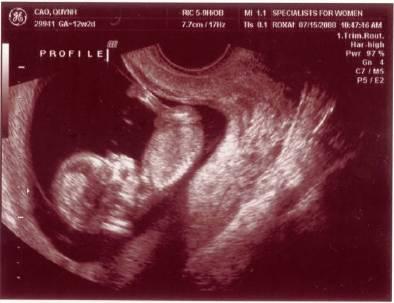

Ngày 11/28/1999 Ba Mẹ có nhau, lúc đó con ở đâu ha? Ngày 5/27/2008, con đây rồi!!! Mới được 2 tuần, là hạt nhân nhỏ xíu trong bụng Mẹ thôi Ngày 6/4/08, lần đầu tiên Ba Mẹ nghe tim con đập, 124 nhịp/phút. Mẹ sung sướng nhìn con. Còn Ba thì rơm rớm nước mắt, hihi!! Ngày 7/8/2008, con được 11 tuần rồi, bắt đầu có tay chân rồi đây... 1 tuần sau tay chân con đã dài ra rồi, lẹ ghê... ...biết nhào lộn vòng vòng nữa, mới nằm úp giờ nằm ngửa rồi. Ngày 9/3/2008, Mẹ chưa muốn biết con là trai hay gái vì muốn bất ngờ, nhưng rồi cuối cùng cũng không đợi được... ...hihi, cục cưng của Ba Mẹ là con trai. Con trai miệng bự giống Ba.  19 tuần là mắt mũi miệng đầy đủ hén. Từ khi biết có con, Mẹ nhờ Ba chụp hình hai mẹ con mình. Cái này là lúc con được 2 tháng trong bụng Mẹ.. ...24 tuần, con bắt đầu cựa quậy lung tung mỗi ngày... ...36 tuần, có lúc Ba Mẹ tưởng đã mất con nhưng con vẫn lớn giỏi ngoan... ..39 tuần, con nặng quá rồi nhưng Mẹ vẫn muốn con ở trong đó thêm chút nữa cho lớn lớn... Ba thì nôn gặp con quá, ngày nào Ba cũng nói chuyện với con.  Bụng Ba cũng bự rồi nè! Ngày 1/20/2009, con 39 tuần, bác sĩ muốn con ra sớm cho an toàn.  Ba Mẹ hồi hộp đợi tới lúc gặp con... Sau gần 8 tiếng chờ đợi thì con ra đời!! Con mở mắt nhìn Mẹ như là biết rồi đó.  Thương con ghê nơi! 1 tuần tuổi thì rụng rún.  2 tuần tuổi thì chụp hình lần đầu với Mẹ, nhỏ xíu xiu xiu... 7 tháng (8/2009) con bò lung tung, chụp hình mà không yên... 14 tháng (4/2010) con chỉ muốn chạy chơi thôi, Ba chụp lẹ lẹ nghe. Ngày 2/19/2010 Ba Mẹ làm lễ cưới ở nhà thờ.  Lần này thì có con rồi.  Có con Ba Mẹ có tất cả...

• Siêu âm